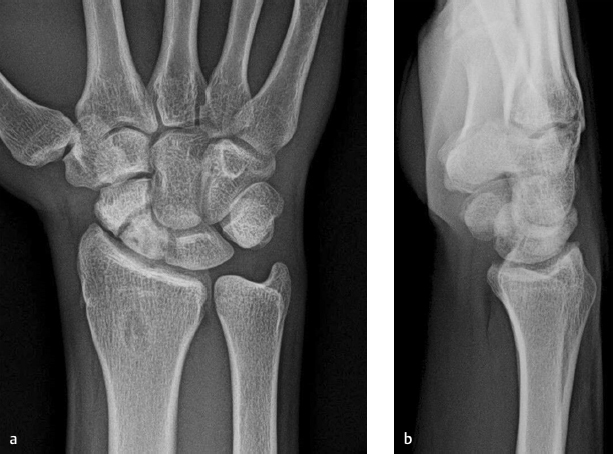

Recalcitrant scaphoid waist nonunion (► Fig. 49.1a,b)

Significant bone loss

Presence of humpback deformity (defined as lateral intrascaphoid angle ≥ 45 degrees)

Absence of radiocarpal arthritic changes

Salvageable proximal pole

Intact cartilage

Proximal fragment is of adequate size for fixation

Without fragmentation or comminution